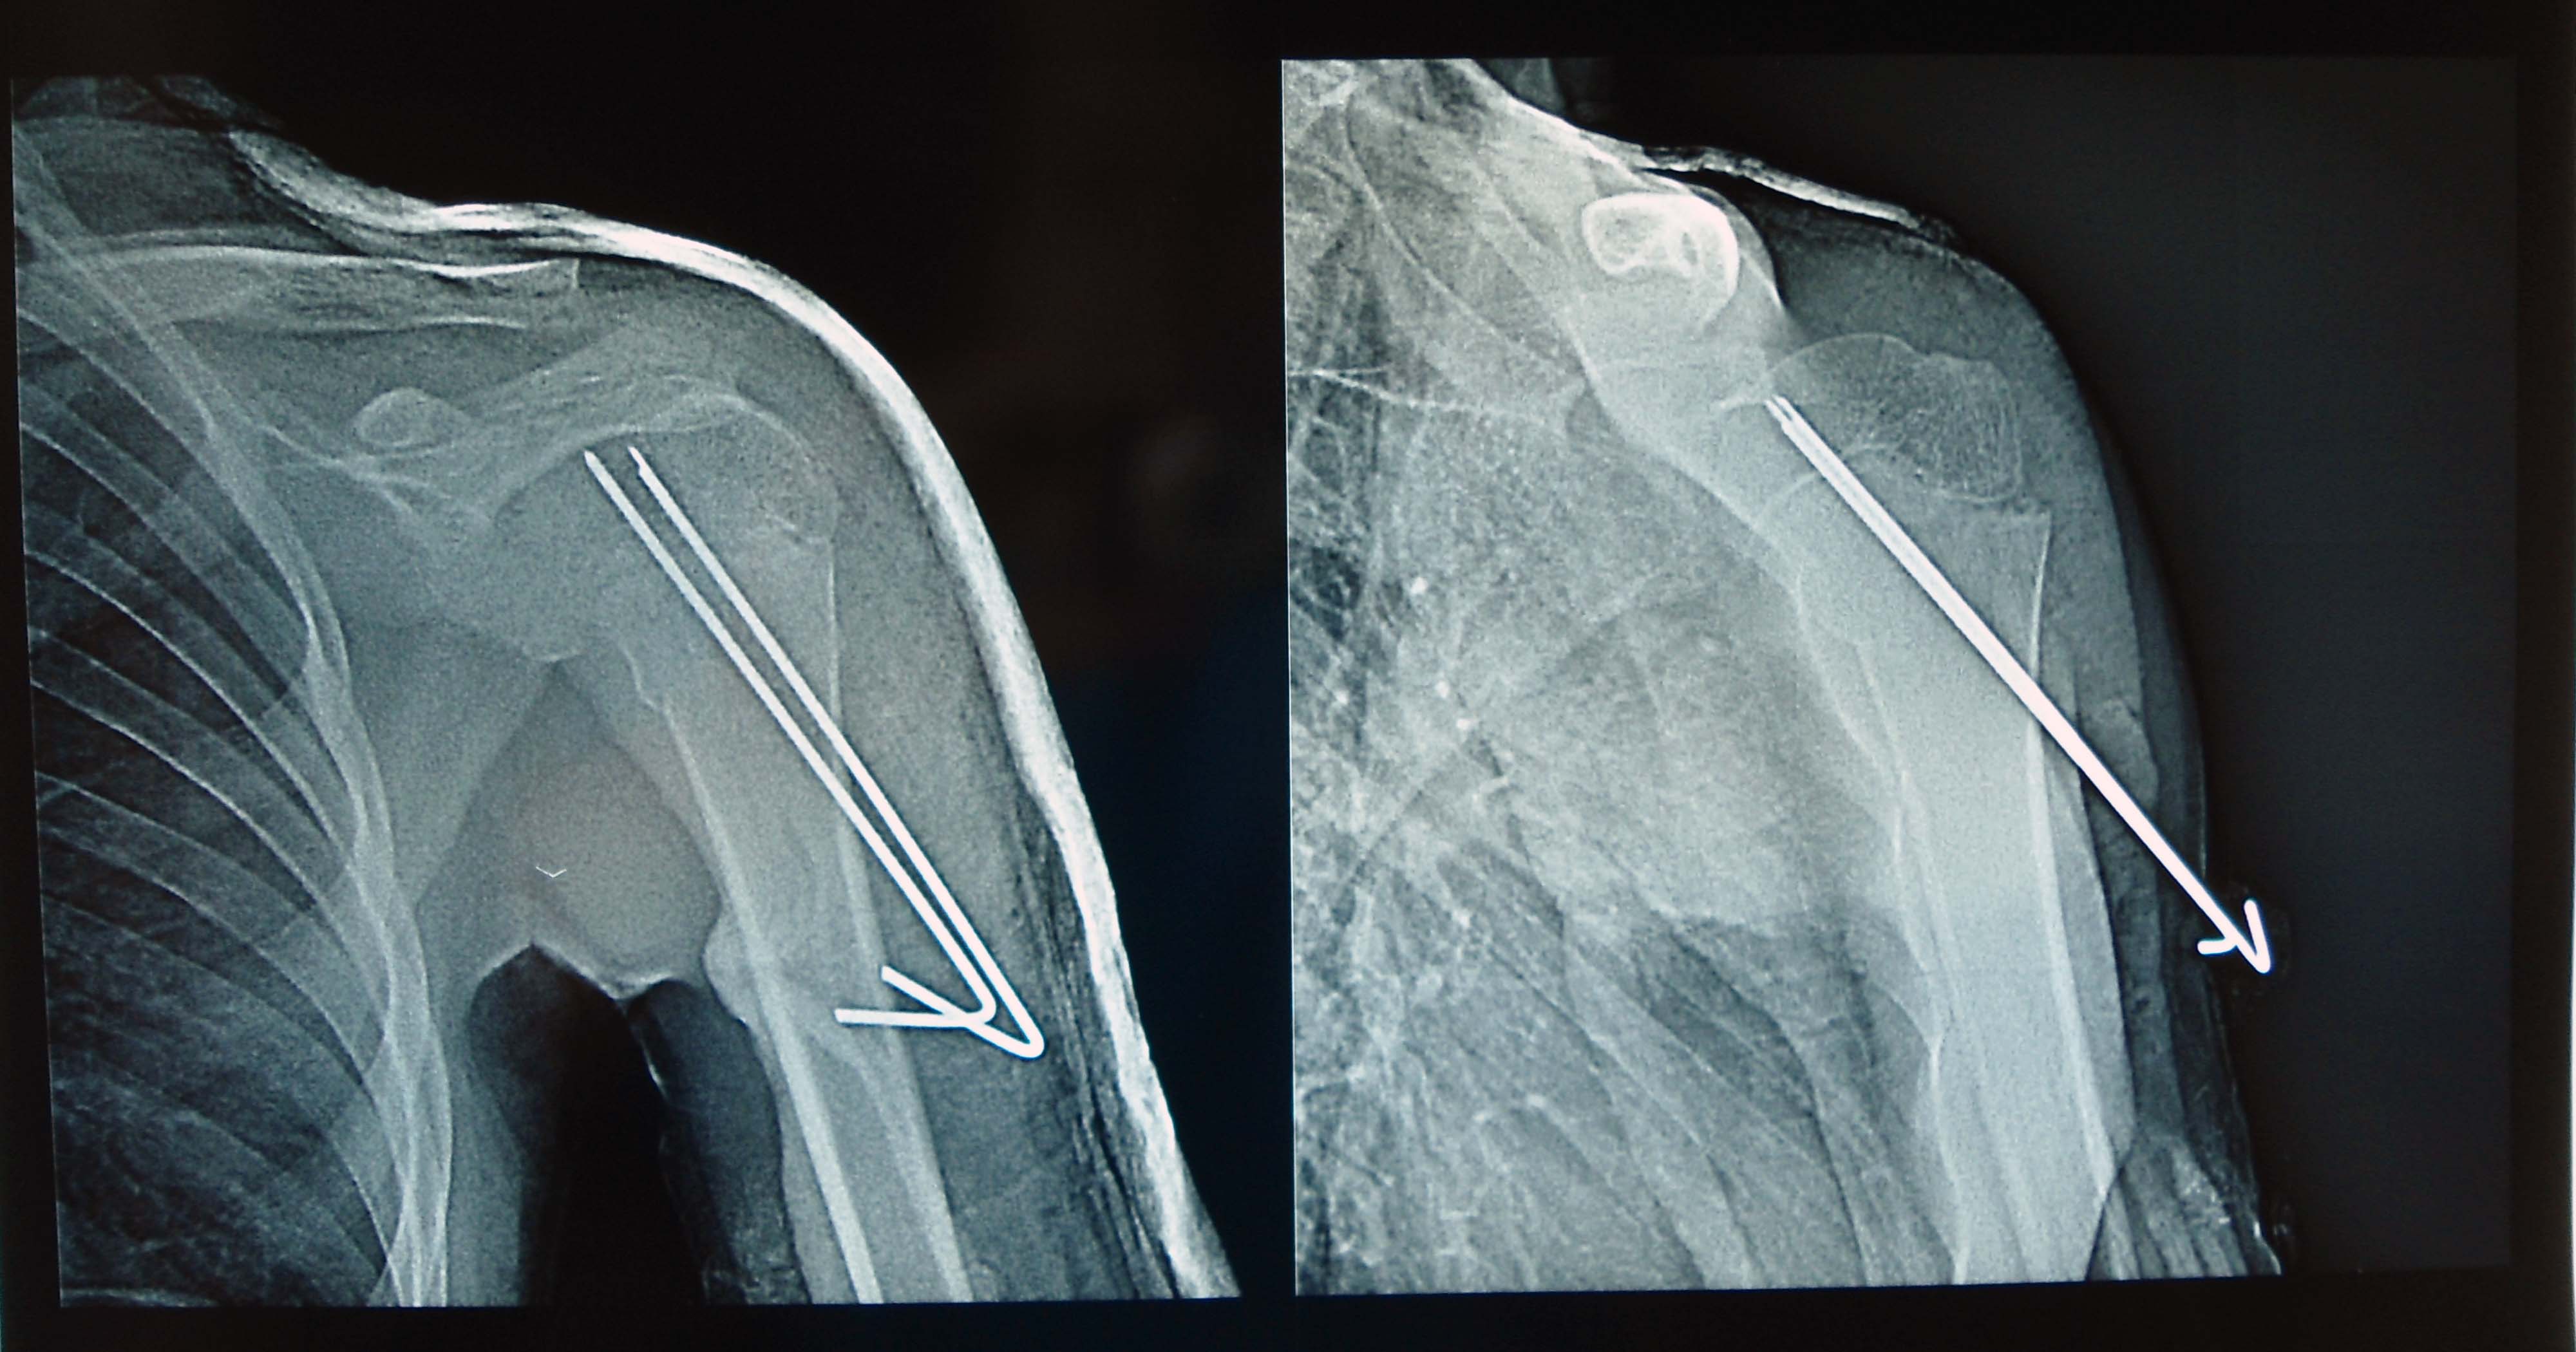

Перелом со спицей

Перелом со спицей 109 фотографий